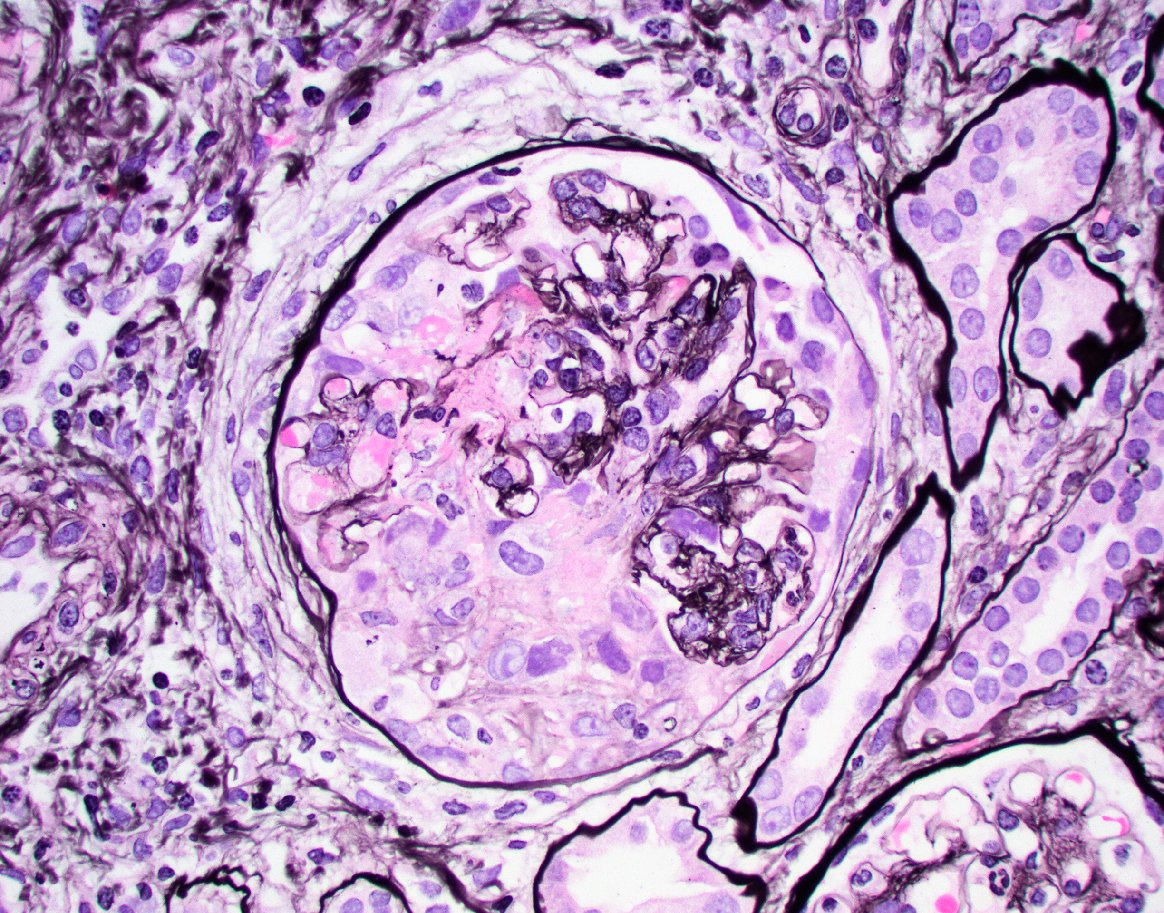

Nice example of medullary angiitis in a case of crescentic pauci immune GN. Characteristic findings include interstitial hemorrhage + PMN rich leukocyte infiltration and karyorrhectic debris. Can also be seen with IgAN, AIN, and cryoGN.  #renalpath #nephrology #pathtwitter